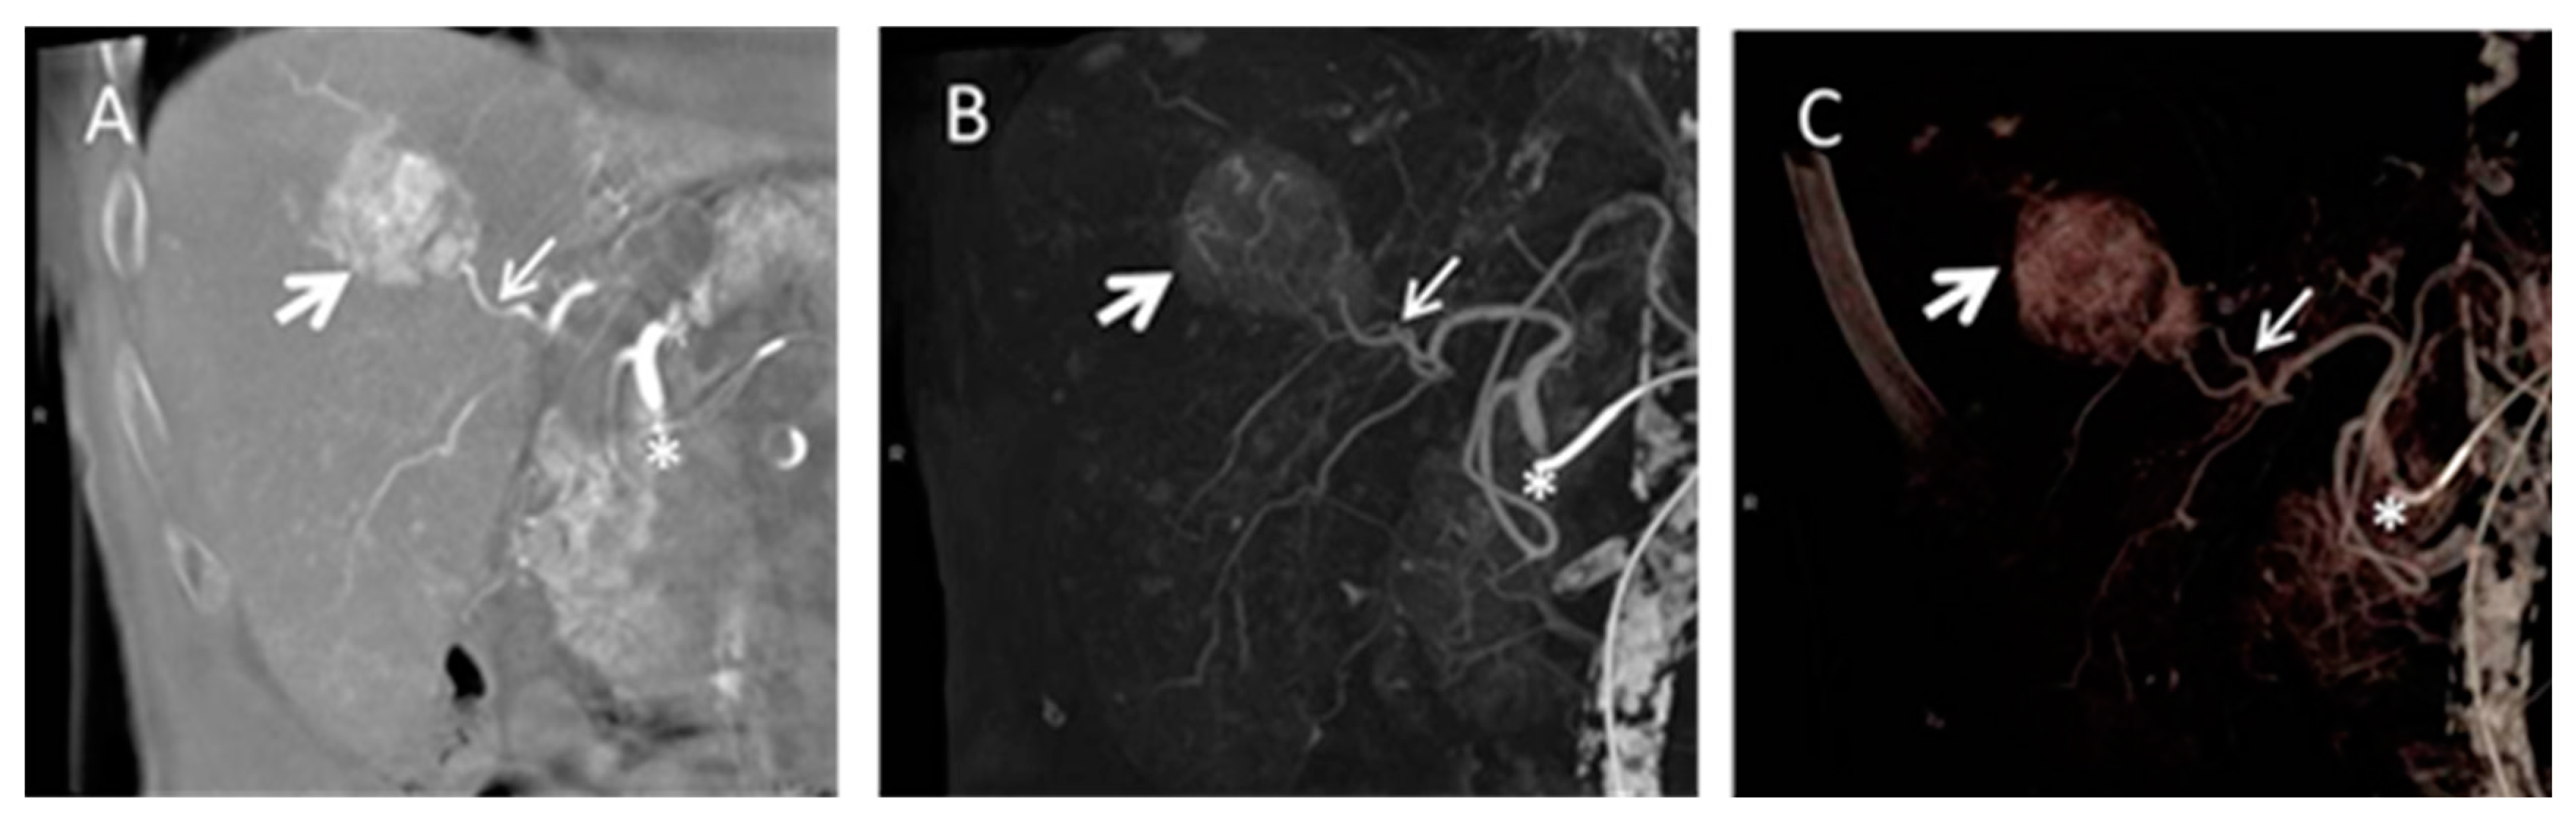

Cone beam computed tomography (CB CT) is increasingly used for peri-procedural assessment of TACE and selective internal radiation therapy (SIRT) in HCC as it shows advantages in immediate pre-interventional treatment planning [140,141,142,143]. In especial, detection of smaller or less vascularised liver tumors is reported to be limited using conventional angiography due to inhomogeneous perfusion in cirrhotic liver tissue [144,145,146]. The main advantage of CB CT as part of an angiographic suite consists of intra-procedural acquisition of 3D volumes of interest and further post-processing including maximum intensity projections (MIP) and multiplanar reconstructions (MPR) comparable to conventional cross-sectional imaging, as well as acquisition of unenhanced and contrast enhanced images of liver parenchyma [140] (Figure 8).

Figure 8. Cone beam computed tomography (CB CT) gained during transarterial chemoembolization (TACE). Coronal multiplanar reconstruction (A), coronal maximum intensity projection; (B) and volume rendering technique; (C) are presented. The tumor volume is marked by the big white arrow and the tumor feeding vessel is marked by a smaller white arrow. The asterisk marks the catheter position in the common hepatic artery.